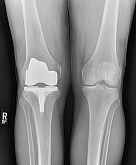

Endoprothetik des Kniegelenks

In den späten Stadien der Arthrose des Knies durch eine ausgeprägte Begrenzung der Bewegung begleitet, konstant starke Schmerzen, körperliche Unversehrtheit Verformung bis zur Genesung der einzige Weg ist der Ersatz des betroffenen Gelenks für eine künstliche - Endoprothetik.

Diese Methode ermöglicht es Ihnen, die richtige Form des Gliedes, eine vollständige Palette von Bewegung im Gelenke, zu entlasten ständige Schmerzen und Knirschen bei Bewegung und als Ergebnis wieder herzustellen, signifikant dem Patienten Lebensqualität zu verbessern.

Im Folgenden sind Röntgenaufnahmen und Fotografien, die die Strecke der Bewegung in der betroffenen Gelenke vor und nach der Operation veranschaulichen.